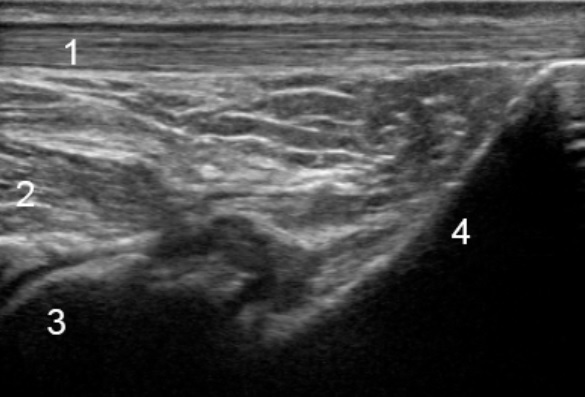

Bild 1: Fuß und Sprunggelenk, posterior, longitudinal

1. Achillessehne

2. Flexor hallucis longus

3. Talus

4. Calcaneus